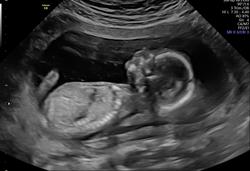

A magzat méretei a 15. héten

A 15 hetes magzat már elég nagy ahhoz, hogy az orvosi vizsgálatok során pontos adatokat lehessen rögzíteni a fejlődéséről. Az alábbiakban összegyűjtöttük a legfontosabb méreteket és orvosi rövidítéseiket:

- Teljes hossza (CRL – Crown-Rump Length, ülőmagasság): kb. 10-11 cm

- Súlya: kb. 50-70 gramm

- Lábszár csont hossza (FL – Femur Length): kb. 1,2-1,5 cm

- Fejkörfogat (HC – Head Circumference): kb. 11-12 cm

- Haskörfogat (AC – Abdominal Circumference): kb. 8-9 cm

- Felkarcsont hossza (HL – Humerus Length): kb. 1,2 cm

A 15. héten a magzat már jelentős mértékben fejlett. Az ultrahangvizsgálatok során jól láthatóak a végtagjai, a fejének formája, valamint az arcvonásai is egyre jobban kirajzolódnak. A kisbabának már kialakultak az ujjai és a lábujjai, és elkezdi gyakorolni a szopó reflexet is. Az arckifejezései és a mozgásai is egyre aktívabbak, amit a kismama még nem mindig érez, de az ultrahang során jól látható.

A 15. héten általában nincs kötelező ultrahangvizsgálat, de sok kismama ekkorra időzíti a második trimeszteri genetikai ultrahangot, amely során az orvos részletesen megvizsgálja a magzatot, hogy meggyőződjön annak megfelelő fejlődéséről és az esetleges rendellenességek kiszűréséről.